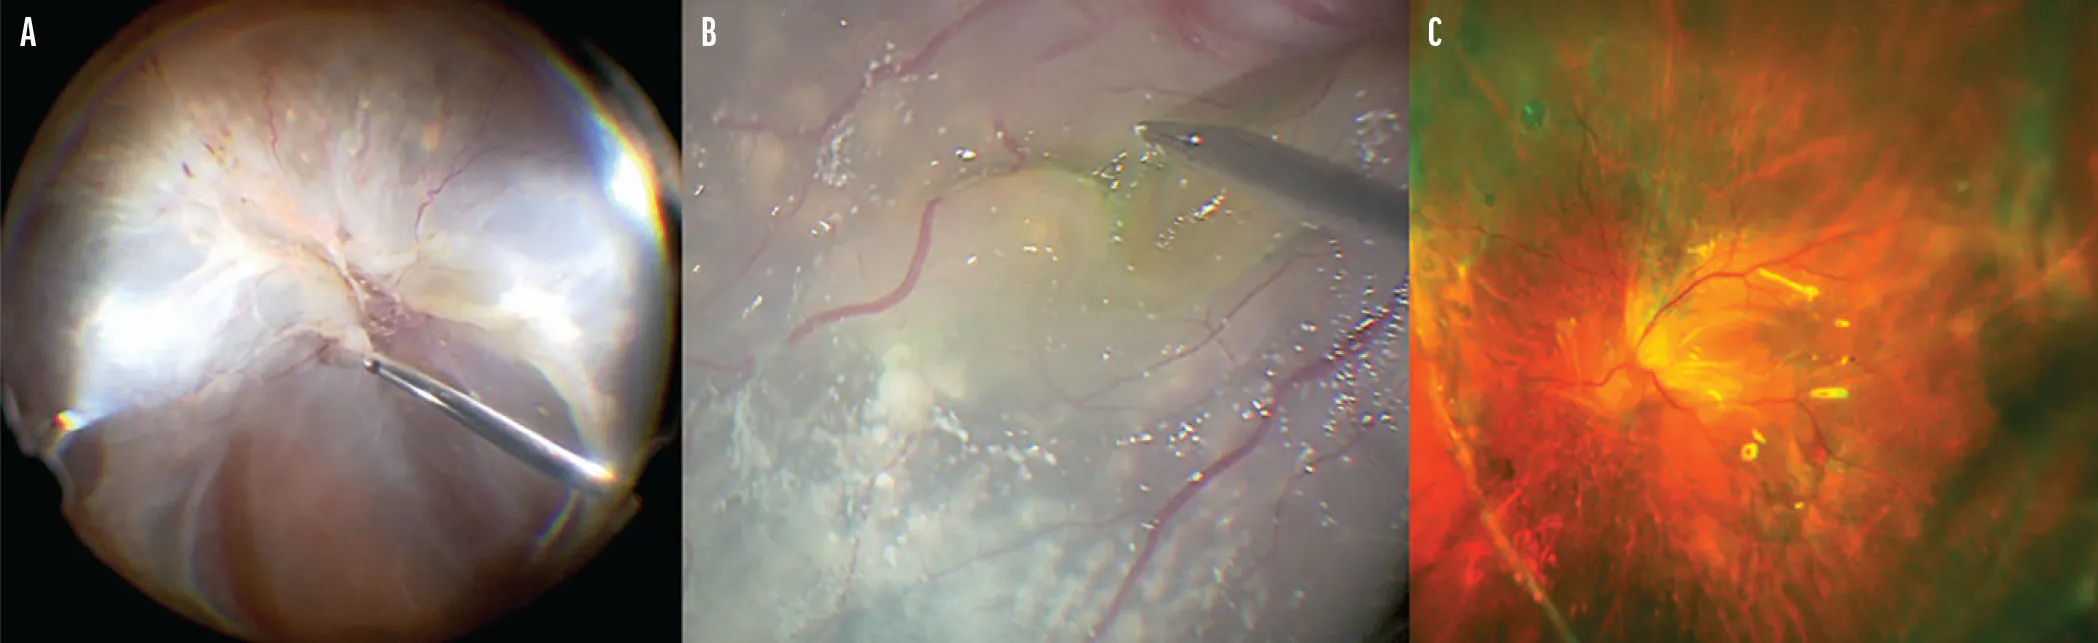

Clinical Applications of Microscope-Integrated OCT

Recent advances have improved the utility of intraoperative visualization, with more innovation on the way.

Bani Aguirre, MD, MPH; Anjali Saini, BS; Vahid Ownagh, MD; and Lejla Vajzovic, MD